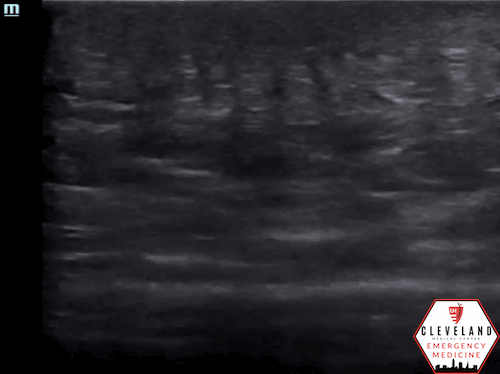

Figure 2. Abscess with echogenic debris, swirling with compression.

• Well-circumscribed, anechoic or hypoechoic fluid collection.

• Often contains hyperechoic debris from pus or necrotic material.

• Walls are usually distinct and hyperechoic.

• Probe compression may produce swirling of fluid, known as the “squish sign” (see Figure 2) [8].